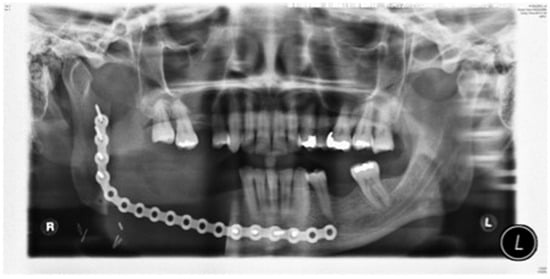

Figure 1.

Clinical case. Orthopantomography (OPT) showing calcifying epithelial odontogenic tumor affecting the right mandible.

Stage 1 surgery. Orthopantomography (OPT) to show locking plate to maintain the position of bony fragments whilst oral mucosa is healing in gun shot wound case.

Figure 11.